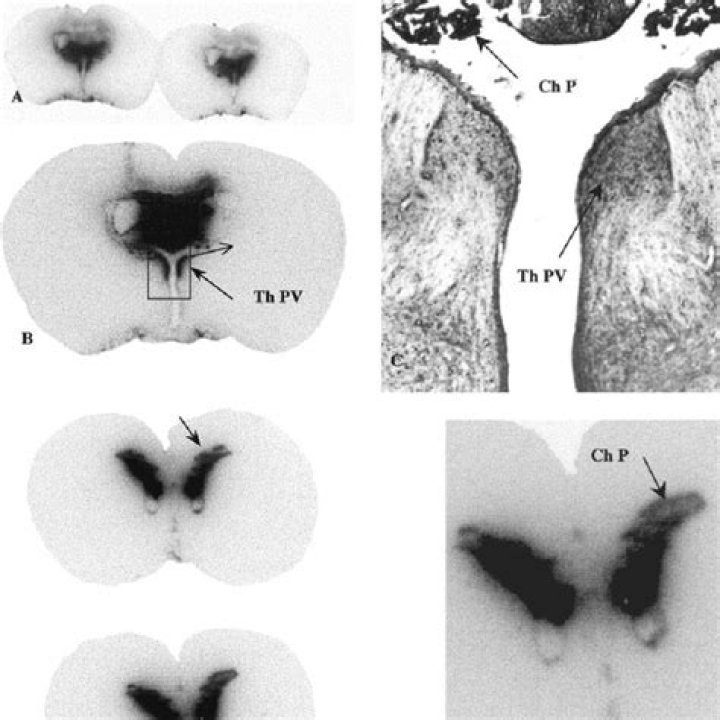

Autoradiography is an imaging technique that uses radioactive sources contained within the exposed sample. ... In in vivo autoradiography, radioisotopes are coupled with radioactive tracers and administered orally or via injection, and the distribution of radiation is evaluated in thin tissue or whole-body cryosections.

A method of in vivo autoradiography was utilized which allows the visualization of local changes in opiate receptor occupation in the intact rat brain. The method is based on the exclusion of [3H]diprenorphine binding in areas in which the release of endogenous opiate peptides is increased by behavioral manipulation.

An autoradiograph is an image on an x-ray film or nuclear emulsion produced by the pattern of decay emissions (e.g., beta particles or gamma rays) from a distribution of a radioactive substance. ... The film or emulsion is apposed to the labeled tissue section to obtain the autoradiograph (also called an autoradiogram).

Quantitative autoradiography of macroscopic specimens using computer-assisted image analysis is now widely used for studying the distribution of peptide receptors in the brain and peripheral tissues and more recently has been used to measure mRNA in tissue sections by in situ hybridisation.